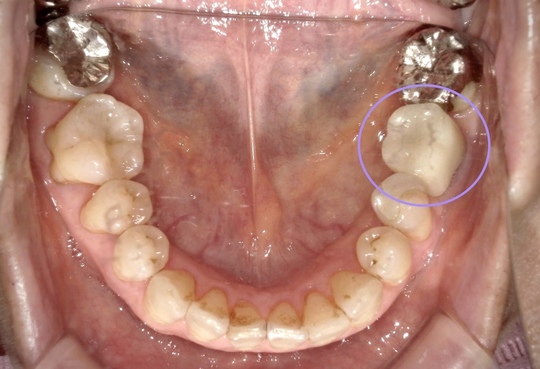

歯の移植治療症例1 治療前

左下の奥歯が根が割れて保存不可能です。奥の咬合わせの余っている親知らずを移すことににしました。移植した歯は、根管治療とクラウン修復が必要です。

3年経過口腔内写真

お手入れもうまくいって炎症もありません。

3年経過口腔内写真

奥から2番目、審美性も機能も維持されています。